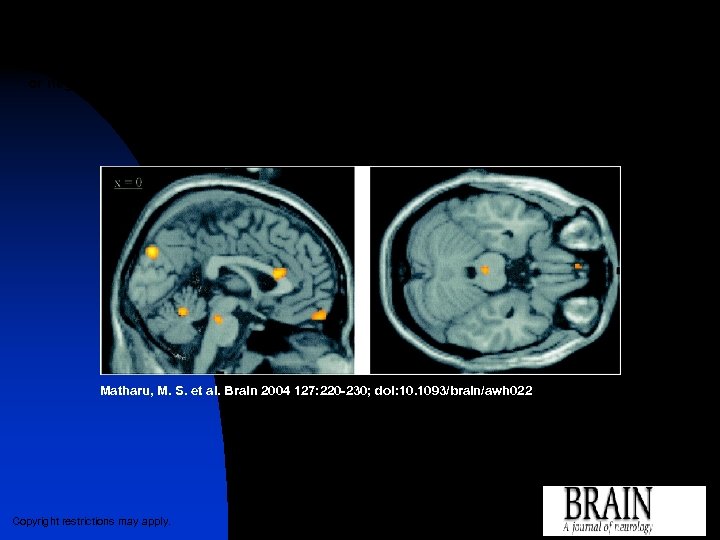

Statistical parametric map (SPM{F}) showing brain regions in which r. CBF correlates (positively or negatively) with pain scores, in particular the dorsal rostral pons, ACC and cuneus (voxels significant at P Matharu, M. S. et al. Brain 2004 127: 220 -230; doi: 10. 1093/brain/awh 022 Copyright restrictions may apply.